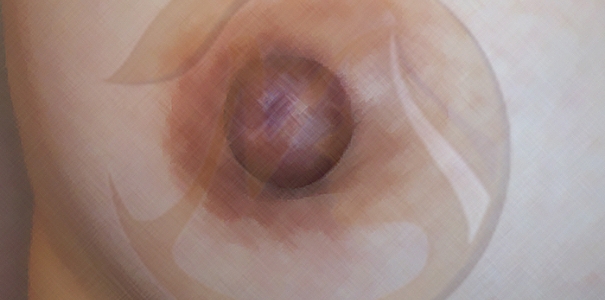

함몰유두란?

함몰유두란 선천적 또는 후천적으로 한 쪽 또는 양쪽 유두가 솟아있지 않고

유방 쪽으로 함몰되어 위생상, 미용상으로 문제를 일으키는 상태를 말합니다.

위생상으로는 함몰된 부위로 유선 등 기타 분비물이 고이고 잘 배출되지 않아 청결 문제는 물론 다양한 합병증까지 유발할 수 있습니다.

미용상으로는 유두가 함몰되어 성적 자신감이 낮아질 수 있습니다.